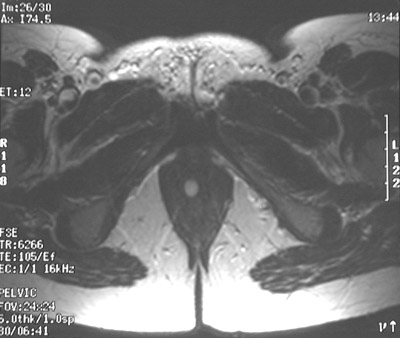

The small bright cystic structure in the lower vagina is a cyst of Bartholin's gland. These paired glands have ducts that can become blocked, and the gland can become cystic or infected and form an abscess.